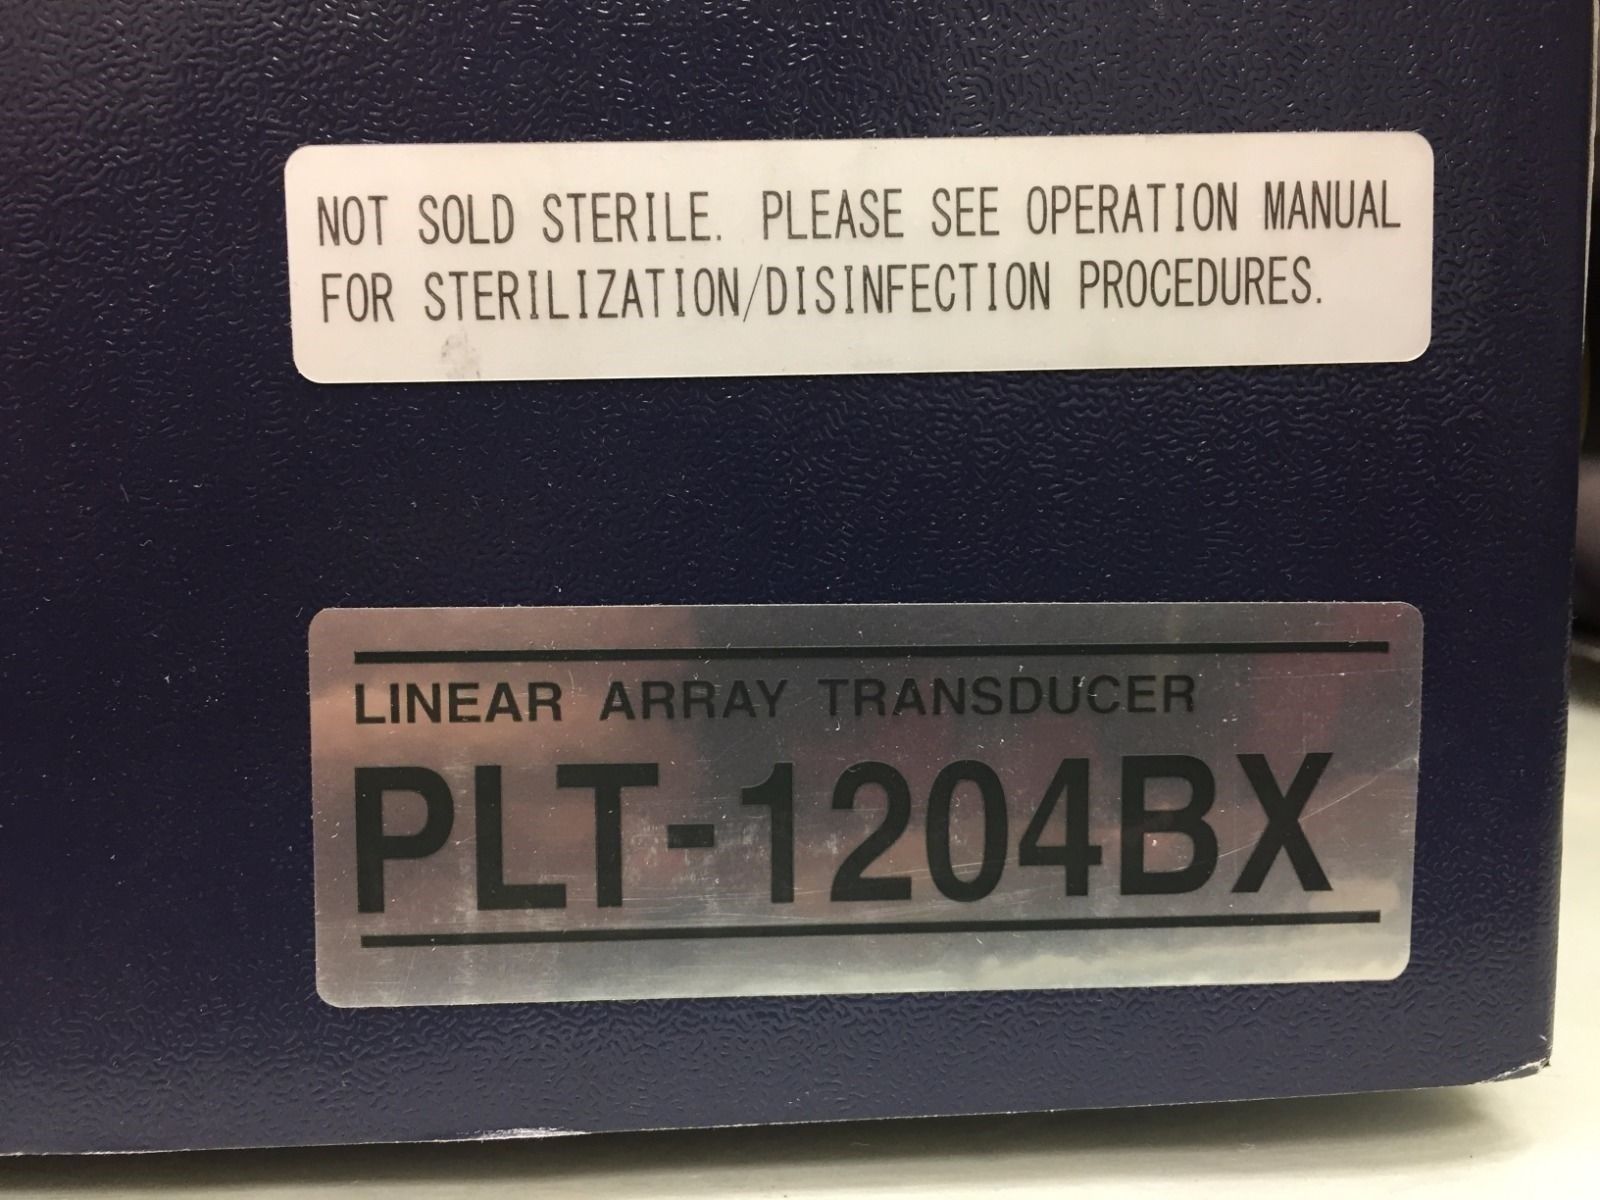

Toshiba Probes

DIAGNOSTIC ULTRASOUND MACHINES FOR SALE